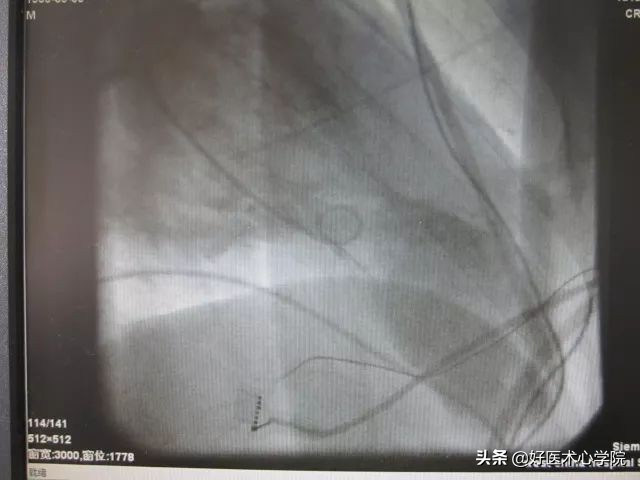

冠脉造影:左右冠状动脉未见异常,左室心尖巨大室壁瘤形成,左心EF:32%。

冠脉造影:左室中部狭窄。